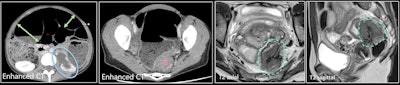

A 39-year-old woman (different from previous figure) with acute clinical intestinal obstruction. Contrast-enhanced CT (first two images) shows small and large bowel distension (green arrows), longstanding left urinary obstruction (blue circle), and mechanical obstruction with rectosigmoid mass (red star). MRI was performed after surgical decompression by colostomy. T2 axial and T2 sagittal images show stellar retractile hypointense T2 mass of the Douglas pouch with colic muscular thickening. Endometriosis of the torus extends transmurally to the rectosigmoid, with stenosis and left ureter involvement."Preoperative diagnosis of appendicitis caused by endometriosis is difficult and therefore rarely made," they said. "Ultrasound of the right iliac fossa with a high-resolution linear transducer is probably the best imaging modality."